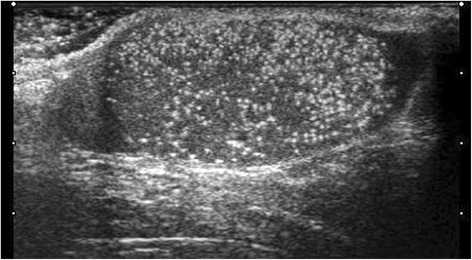

Testicular microlithiasis (TML) corresponds to concretions of hydroxyapatite surrounded by fibrosis located in the seminiferous tubes [1]. They are due to the insufficient capacity of Sertoli cells to phagocyte the degenerate cells present in these tubes. They are commonly discovered by ultrasound (US). They are not visible on Magnetic Resonance Imaging (MRI). In 1987, Doherty et al. [2] described their appearance on US, which is characterized by a hyperechoic focus measuring between 1 and 3 mm in the testicular parenchyma without posterior shadow cone [3] with a number greater than or equal to 5 per testis. The discovery is mostly fortuitous because there is no clinical manifestation. Their historical radiological classification is described by Backus et al. [4]. Three grades are distinguished according to the number of TML described by parenchyma (grade 1: 5 to 10, grade 2: 10 to 20 and grade 3 with more than 20 TML). In recent years, US has substantially improved with the advent of higher resolutions enhancing TML detection. In 2015, the European Society of Urogenital Radiology (ESUR) proposed a summary of guidelines and reported another classification with 3 groups, based on the number of TML per field of vision [5]. These three groups were defined as follows, limited TML: less than 5 per field of view (Fig. 1), classic TML: greater than or equal to 5 per field of view (Fig. 2) and finally diffuse TML, labelled “snowstorm” (Fig. 3). There are many observational studies on TML and testicular cancer risk. The objective was to perform a review of the available literature to date.

Fig. 3.

Diffuse testicular microlithiasis (TML). With agreement from authors [8]